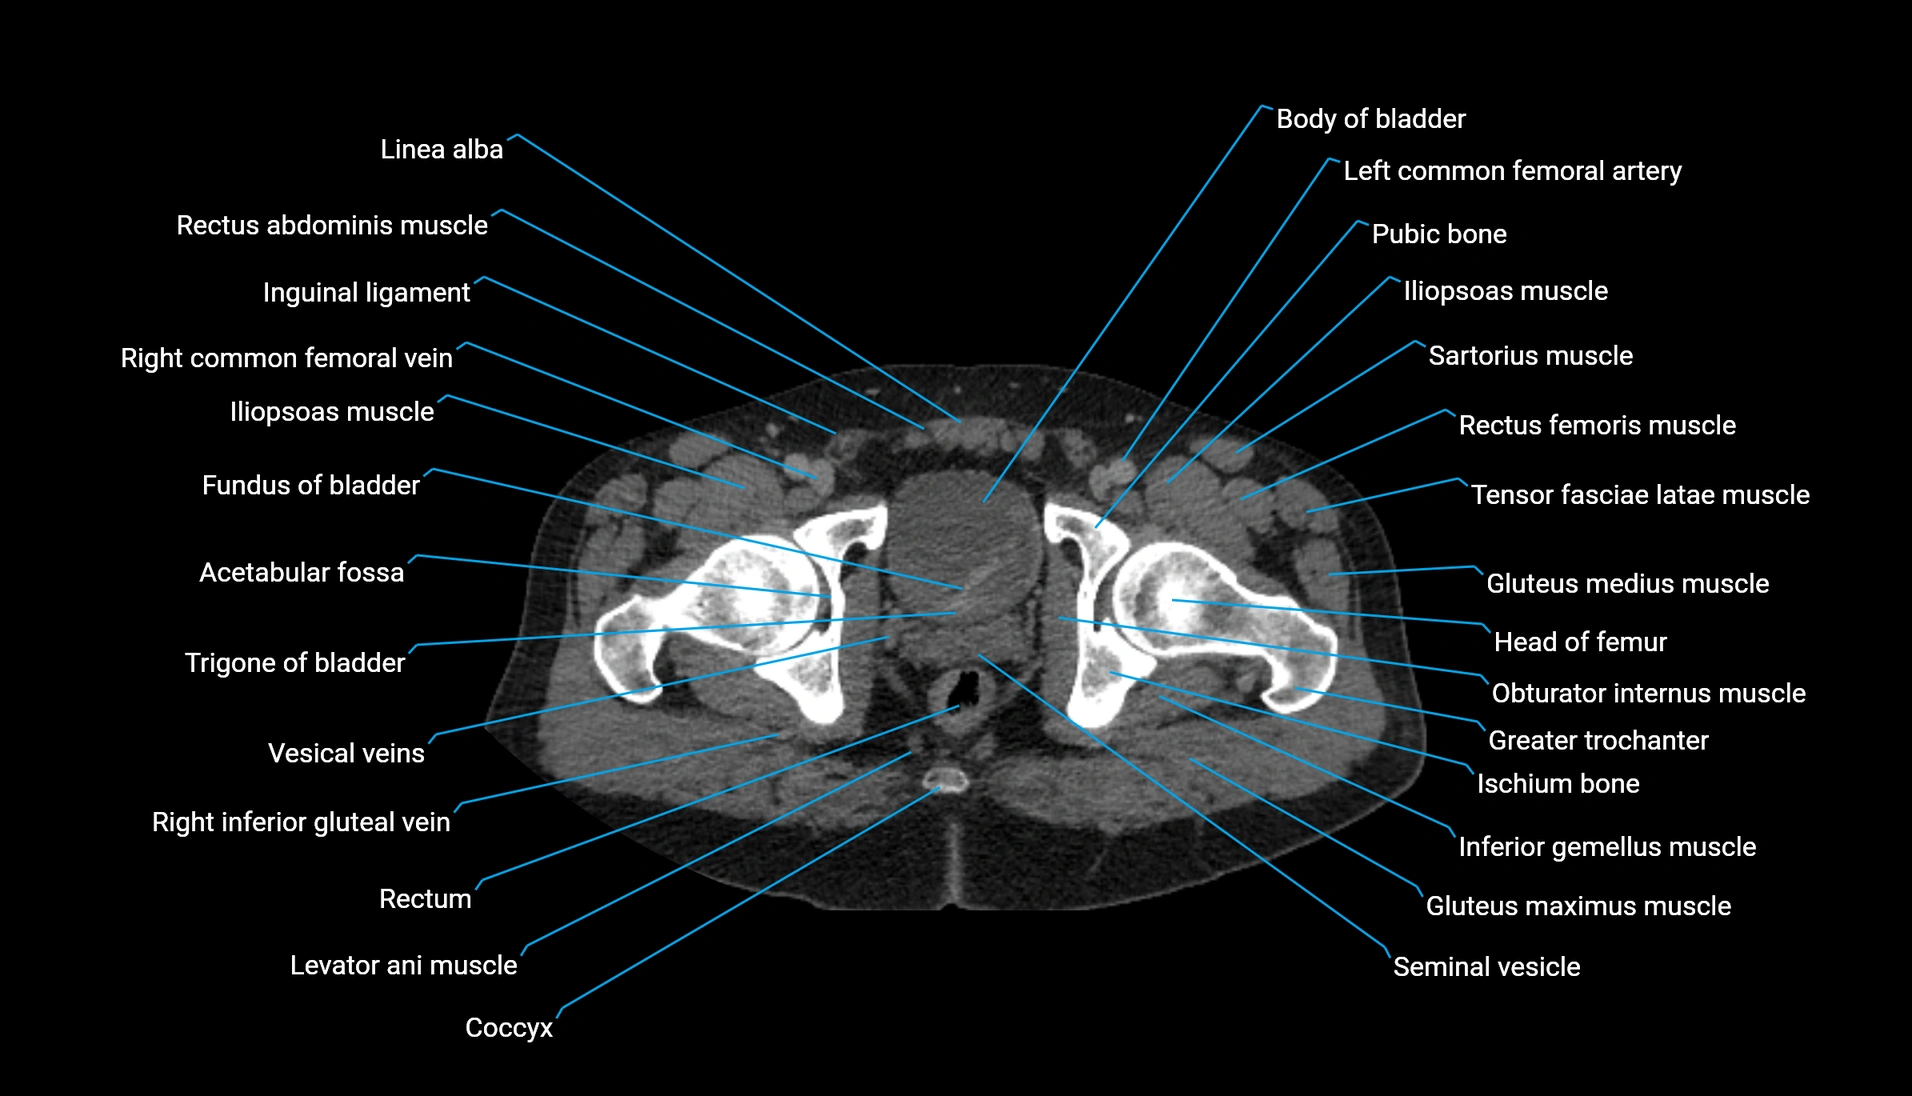

CT Appearance

Non-contrast CT:

-

Demonstrates cortical bone of acetabular rim in excellent detail

Detects fractures, dysplasia, retroversion, or bony overcoverage (pincer impingement)

3D reconstructions used in preoperative hip surgery planning

CT image